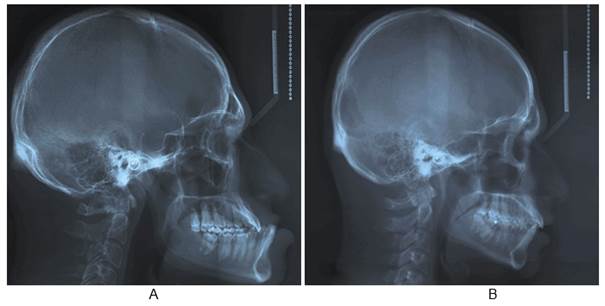

Both radiographs were obtained (Fig. 1), and a cephalometric analysis was performed using some angular measures commonly used in orthodontics13. Subsequently, two cephalometric superimpositions were conducted: one general and one mandibular, both based on the method proposed by Björk23-25. This allowed us to see the areas with the greatest craniofacial morphological change in the acromegalic patient with respect to his twin brother.

Table 1 summarizes the cephalometric values of both twins and the differences between them. The Ba-S-N angle was larger in the acromegalic patient (136°) compared to his twin brother (126°). Something similar occurred with the SNB values (96° vs. 85°). There were no significant changes in the SNA angle (89° vs. 90°). The S-Ar-Go angle was reduced in the acromegalic patient (120°) compared to his brother (146°). The ANB angle was greatly altered in the acromegalic patient (-7º) with a difference of 12° compared to his twin brother (5º). The S-N/Go-Gn angle was reduced by 5° compared to his brother (20° vs. 25°). Finally, the goniac angle was increased by 5° (125° vs. 120°). Dentally, there was a greater proinclination of the upper incisors in the acromegalic patient (130° vs. 126°). Fig. 2 shows the cephalometric tracings of both the acromegalic patient and his twin brother.